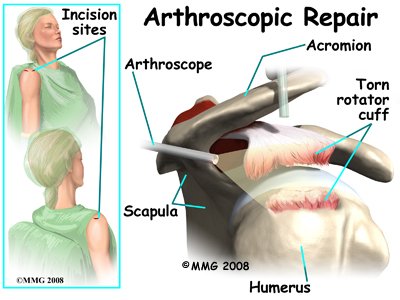

Arthroscopic Repair

In the past, repair of the rotator cuff tendons usually required an open incision three or four inches in length. As surgeons have become more comfortable using the arthroscope to work in and around the shoulder joint, things have changed. Today, it is much more common to repair tears of the rotator cuff using the arthroscope.

In the past, repair of the rotator cuff tendons usually required an open incision three or four inches in length. As surgeons have become more comfortable using the arthroscope to work in and around the shoulder joint, things have changed. Today, it is much more common to repair tears of the rotator cuff using the arthroscope.

An arthroscope is a special type instrument designed to look into a joint, or other space, inside the body. The arthroscope itself is a slender metal tube smaller than a pencil. Inside the metal tube are special strands of glass called fiberoptics. These small strands of glass form a lens that allows one to look into the tube on one end and see what is on the other side - inside the space. This is similar to a microscope or telescope. In the early days of arthroscopy, the surgeon actually looked into one end of the tube. Today, the arthroscope is attached to a small TV camera. The surgeon can watch the TV screen while the arthroscope is moved around in the joint. Using the ability to see inside the joint, the surgeon can then place other instruments into the joint and perform surgery while watching what is happening on the TV screen.

The arthroscope lets the surgeon work in the joint through a very small incision. This may result in less damage to the normal tissues surrounding the joint, leading to faster healing and recovery. If your surgery is done with the arthroscope, you may be able to go home the same day.

To perform the rotator cuff repair using the arthroscope, several small incisions are made to insert the arthroscope and special instruments needed to complete the procedure. These incisions are small, usually about one-quarter inch long. It may be necessary to make three or four incisions around the shoulder to allow the arthroscope to be moved to different locations to see different areas of the shoulder.

A small plastic, or metal, tube is inserted into the shoulder and connected with sterile plastic tubing to a special pump. Another small tube allows the fluid to be removed from the joint. This pump continuously fills the shoulder joint with sterile saline (salt water) fluid. This constant flow of fluid through the joint inflates the joint and washes any blood and debris from the joint as the surgery is performed.

A small plastic, or metal, tube is inserted into the shoulder and connected with sterile plastic tubing to a special pump. Another small tube allows the fluid to be removed from the joint. This pump continuously fills the shoulder joint with sterile saline (salt water) fluid. This constant flow of fluid through the joint inflates the joint and washes any blood and debris from the joint as the surgery is performed.